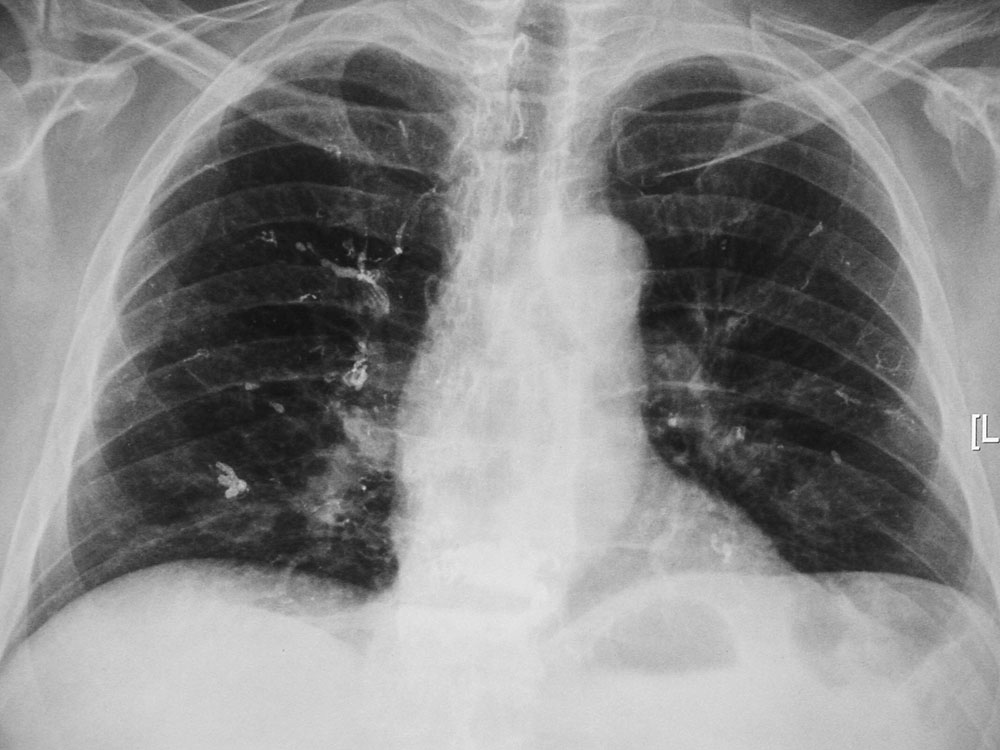

Deliberate injection of mercury subcutaneously or intravenously produces a dramatic radiographic appearance (figure: mercury in left elbow; figure: mercury in the lungs). Individuals may inject themselves in the mistaken belief that mercury increases their strength, or they may be drug abusers or even attempting suicide (Naidich, 1973; Wenzel, 1980; Peterson, 1980; Spizarny, 1987).

If mercury is injected into subcutaneous tissues, it forms irregular globules and may remain in place for months to years. If it is injected into the venous system, it will embolize to the lungs where it forms small globules in the peripheral branches of the pulmonary arteries. The mercury may also pool in the right ventricle. Differentiating aspirated metallic mercury from mercury embolism to the lungs is difficult on the basis of chest radiographic appearances alone. The diagnosis depends on the patient history, presence of mercury in the right ventricle or subcutaneous tissue of the arm or leg (favoring mercury embolism) or the presence of mercury in the gastrointestinal tract (favoring mercury aspiration) (Wenzel, 1980; Peterson, 1980; Spizarny, 1987). Surprisingly, metallic mercury in the bronchial tree or in the pulmonary arterial tree is usually not associated with symptoms, and it may remain undiscovered indefinitely.

21 year-old man who injected himself with metallic mercury.

21 year-old man who injected himself with metallic mercury. There are mercury emboli to the lungs and metallic mercury is evident in the antecubital fossa of the left elbow. (Figures courtesy of Charles A. Rohrmann, Jr, MD. They were originally printed in Peterson, 1980). Trick or treat candy. There are no hidden needles or razor blades. The candy and the apple (round density) where eaten with much enjoyment. From Hunter, 1994